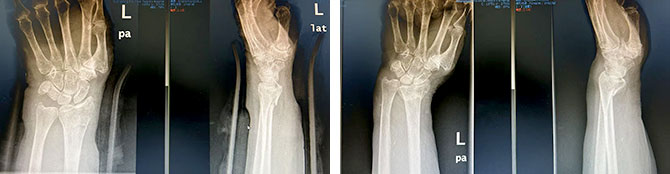

成人桡骨远端骨折(屈曲型)

复位前 复位后